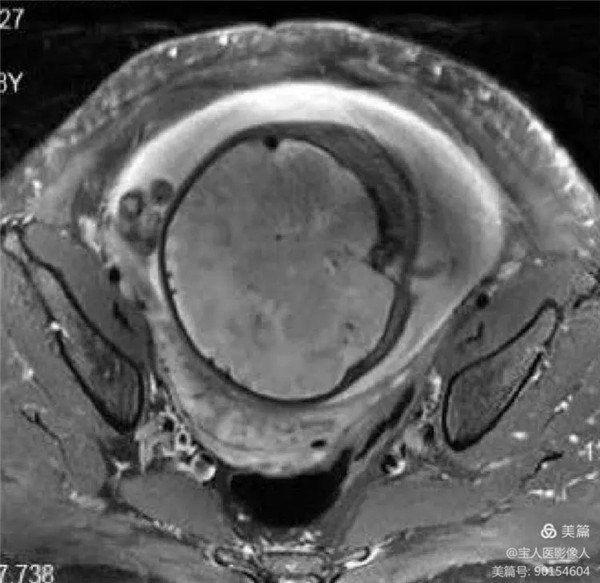

病例11:患者前置胎盘、血管前置、胎盘穿透性植入

图4,轴位fs-T2WI-显示胎盘内信号特点